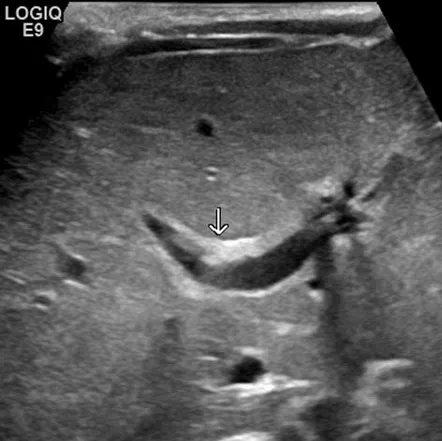

- Ultrasound: Triangular cord sign.

ā Triangular cord sign on US is highly suggestive.